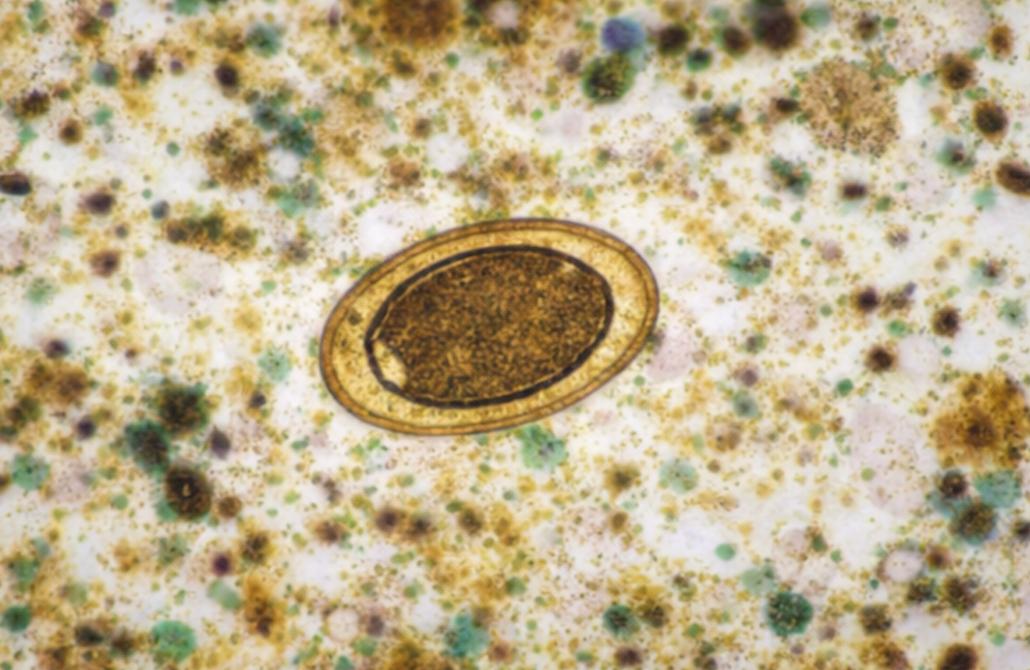

Stool Analysis

Comprehensive detection of parasites, ova, and other diagnostic indicators in stool samples with enhanced visualization